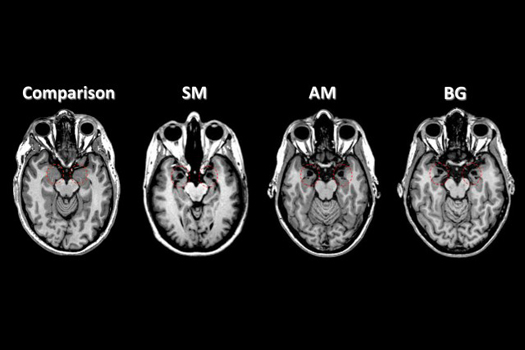

There are some clues here and there as to how it might work. For example, one study found that in people given fake pain-relieving cream experienced less activity in pain-sensing regions of the brain. Another found a similar fake cream activated cells in the spinal cord (see the above image). But how the exact process maps across a whole host of experiences—from fighting infection, to performing better on tests, to sleeping better—nobody really knows.